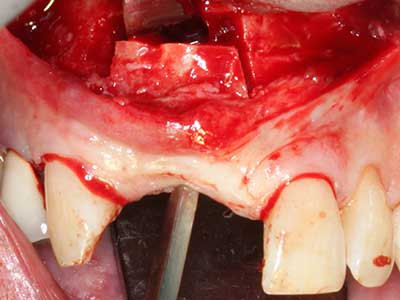

Sollen chirurgische Eingriffe mit unmittelbarer Knochenbeziehung an empfindlichen Strukturen wie Blutgefäßen oder Nerven erfolgen, so bergen rotierende Instrumente ein erhebliches Potential an iatrogener Schädigung. Gerade bei Nervdarstellungen nach iatrogener Schädigung, oder aber im Zuge einer Nervlateralisation für resektive und rekonstruktive Eingriffe oder Implantatinsertionen können piezoelektronische Geräte hilfreich sein Knochendeckel zu präparieren und nervnahe Hartgewebsanteile zu entfernen (Abb. 17-20). Ein leichter Kontakt des Nervstrangs zur Piezospitze bleibt dabei in der Regel folgenlos – allerdings kann eine unvorsichtige Vorgehensweise mit sägeartigen Bewegungen bzw. Ansätzen bei noch vorhandener knöcherner Unterlage durchaus temporäre oder aber auch permanente Nervschädigungen verursachen. Das Risiko einer solchen Schädigung wird jedoch als wesentliche geringer eingeschätzt als unter Anwendung von Säge- oder Fräsinstrumenten (Pereira, Gealh et al. 2014).